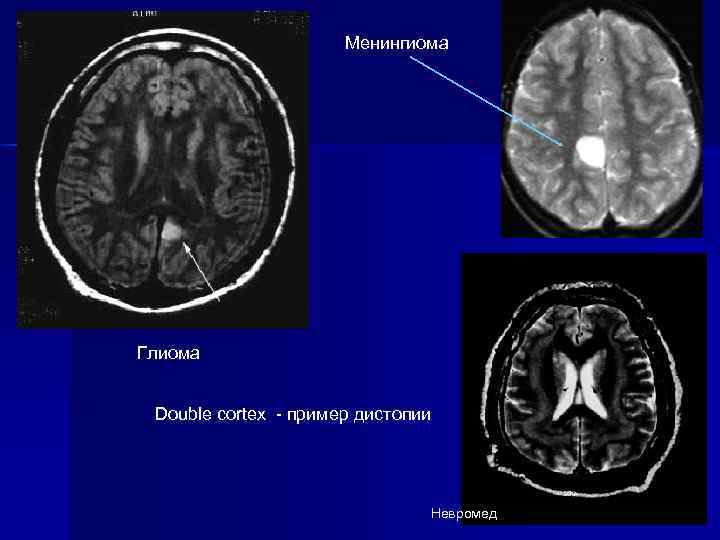

Менингиома Глиома Double cortex - пример дистопии Невромед